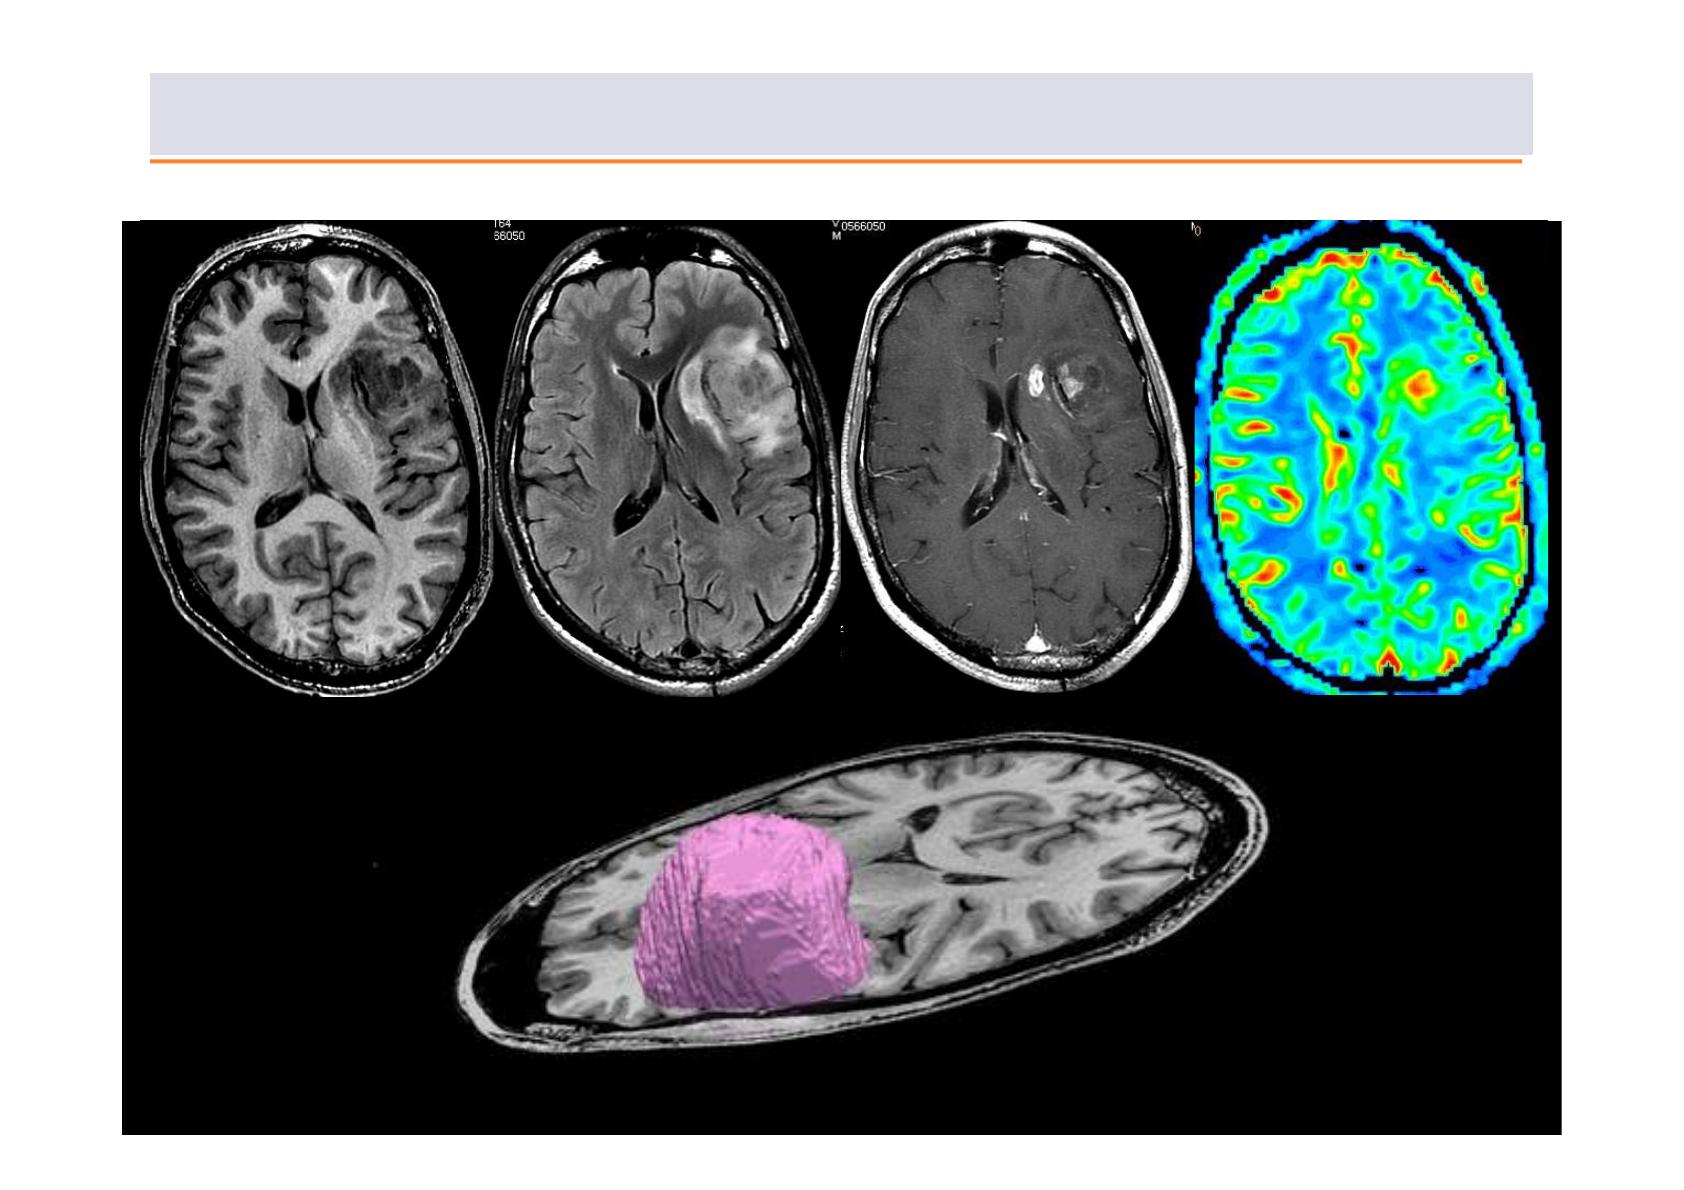

Un exemple : les tumeurs gliales (gliomes)

Exploration multimodale IRM des tumeurs cérébrales

Perfusion

T1 FLAIR Injection